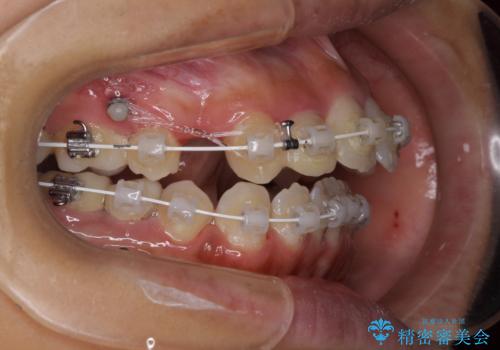

- 矯正装置

- 審美装置

元々むし歯の処置歯が多く、神経を取り除いている歯が多くありましたが、どうやら右上の前歯と小臼歯は外傷により神経を失った可能性があり、抜歯したスペース前後の歯が全く動かない状態でした。

結果として下顎の小臼歯は抜歯せず、右上の抜歯スペースはむし歯処置を兼ねてオールセラミックブリッジにて補綴治療を行うこととしました。

動かない歯での停滞や、出産と子育てなどにより治療期間は長期化しましたが、整った歯列にて仕上げることができました。